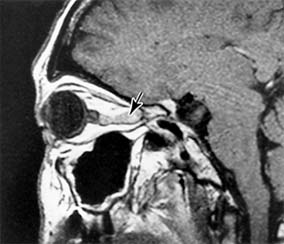

Primary optic nerve sheath meningioma is a rare tumor most commonly presenting, like other types of meningioma, in middle-aged women (Figure 14-19). Five percent of cases are bilateral. Visual loss is slowly progressive. The classic clinical features are a pale, slightly swollen optic disk with retinochoroidal collaterals, but in most cases the collateral vessels are not present (new window  Figure 14-6). Surgical excision invariably leads to complete loss of vision and is generally reserved for blind eyes to prevent intracranial spread of tumor. Focal radiotherapy is becoming more popular.

Figure 14-19

Figure 14-19: MRI of tubular optic nerve sheath meningioma.